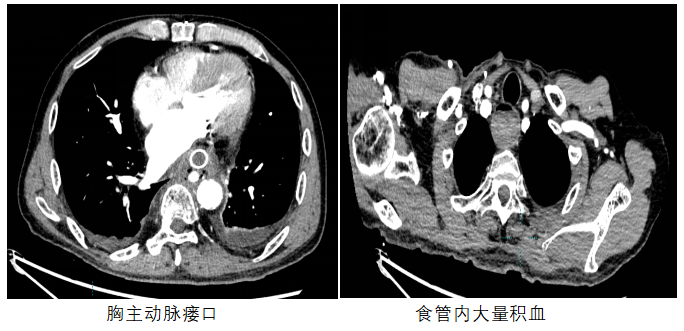

面对紧急情况,在方主亭副院长指挥下,重症医学科叶勇主任团队、介入科陈示光主诊团队迅速集结,开展一系列紧急治疗措施——气管插管、输血、补液和使用血管活性药物,患者的生命体征逐渐趋于稳定。胸主动脉CTA检查明确为AEF后,团队一致决定采取胸主动脉腔内隔绝治疗。

在与患者家属充分沟通并征得同意后,方主亭副院长带领陈示光主诊团队迅速、精准实施了手术。术中清晰显示造影剂从胸主动脉破口流入食管。经过一系列精细的介入操作,支架成功贴合胸主动脉,精准隔绝破口。术后造影确认破口已被有效封闭,张先生呕血、黑便等消化道出血症状消失,血红蛋白水平逐渐回升,急性上消化道大出血得到了有效控制。